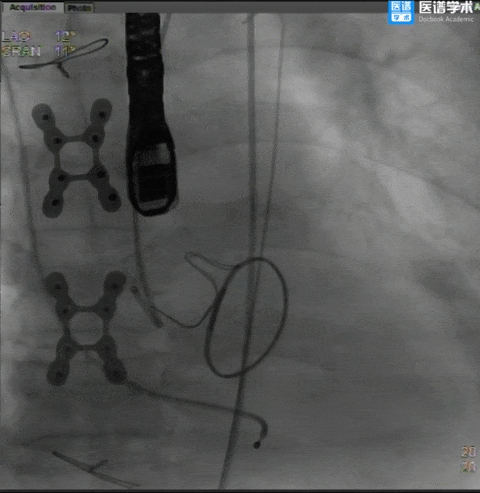

手术过程

主动脉根部造影

球囊预扩

TaurusElite®顺利过弓

TaurusElite®首次释放

TaurusElite®首次回收

TaurusElite®二次释放

TaurusElite®二次回收

TaurusElite®最终释放形态